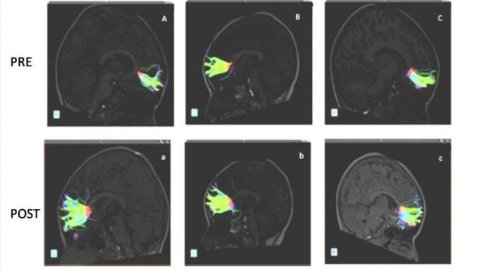

An advanced MRI technique (DTI or “diffusion tensor imaging”) was used to scan their brains before and after music lessons, which took nine months.  DTI can identify microstructural changes in the brain’s white matter

Fibers belonging to the greater forceps pre-musical training are observed (A, B, C). Fibers belonging to the same patients after 9 months of musical training are observed below (a, b, c). Credit: Radiological Society of North America

The study revealed improvement in connections after the nine months of studying music.  Water molecules moved along the fibers better and the fibers themselves were longer, most significantly in the “minor forceps” – a part of the frontal cortex of the brain, which was associated with autism in prior studies.